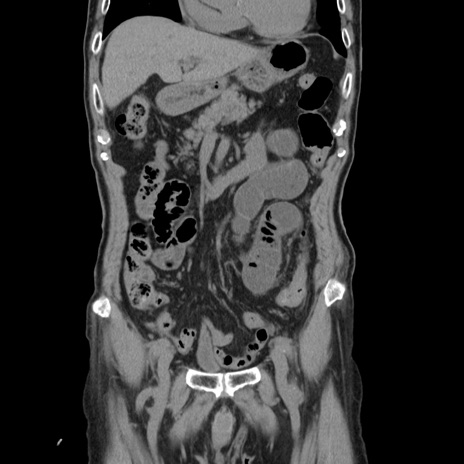

症例24(冠状断像)

【症例】80歳代男性

【主訴】左側腹部痛、嘔吐

【現病歴】本日早朝より左腹部に痛みあり。昼頃嘔吐認めたため、救急要請。

【既往歴】直腸癌(Mile手術)、胆摘

【身体所見】意識清明、BT 35.9℃、BP 221/93mmHg、SpO2 97%(RA) 、腹部:左ストーマ周囲に限局性の腹部膨隆あり。 膨隆部自発痛・圧痛あり・軟。

【データ】WBC 7700、CRP 0.09